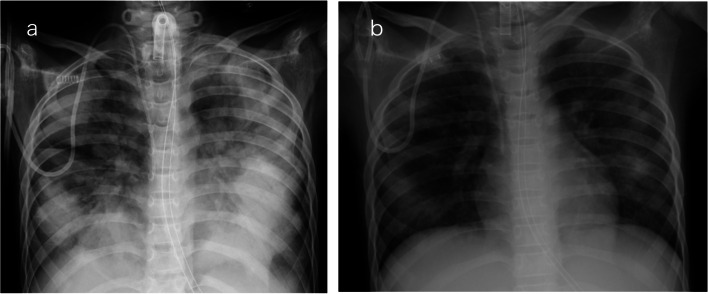

Background: Negative-pressure pulmonary edema (NPPE) often develops with upper airway obstruction, and is uncommon in secured airways, for example, after tracheostomy. Herein, we report two cases of NPPE post-tracheostomy.

Case presentation: Case 1: A 69-year-old man underwent prophylactic tracheotomy for possible airway obstruction secondary to glottic carcinoma. Two hours after awakening from general anesthesia, he had difficulty expectorating and developed NPPE due to airway secretions obstructing the tracheostomy tube. Case 2: An 11-year-old boy was admitted to the intensive care unit for continuous hemodiafiltration on a ventilator under sedation. On the 76th day, the day after the tracheostomy was performed, the patient developed patient-ventilator asynchrony due to sedative withdrawal syndrome. The postulated primary mechanism was functional airway obstruction due to patient-ventilator asynchrony.

Conclusion: These cases highlight the need to consider NPPE, even in patients with an airway secured with a tracheostomy.